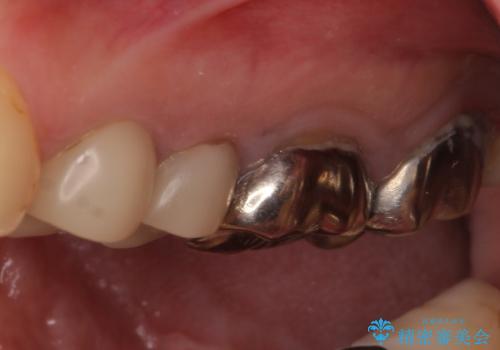

- 笑ったときに見てしまう上顎奥歯の銀歯を気にして来院された患者様です。

折角セラミッククラウンを装着するので、根管治療を行った後に補綴治療を行うこととしました。

他にも目立つ銀歯がありましたが、最も気にしている2本を優先して行うこととしました。

結婚式前にはクリーニングやホワイトニングを行い、その後他の歯を治療していく予定です。